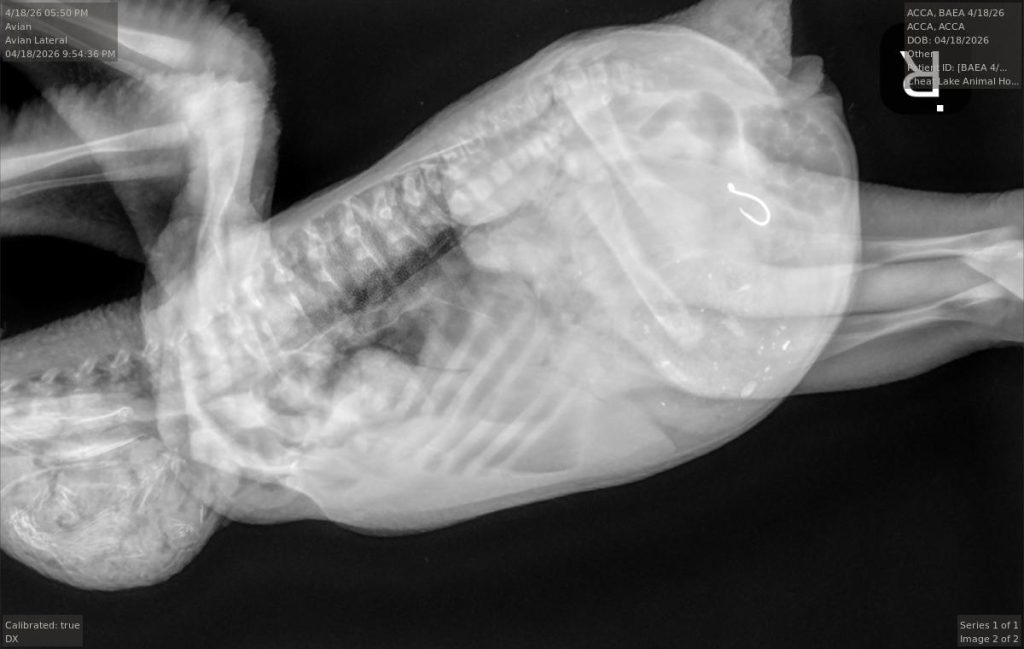

Dr. Jesse Fallon, director of veterinary medicine for the center and a veterinarian at Cheat Lake Animal Hospital where the center is based, took over the story from there. “We decided that the best chance for the eagle to have a positive outcome was to capture it and get that fishhook out of there,” he said.

Fallon and his team examined it when it arrived. The bird was quiet and responsive, had the fishing line hanging out of its mouth, but was otherwise in reasonable health for a 2-week-old eagle chick.

They first tried using endoscopy – a camera on a scope – but there was too much food in the bird’s stomach to be able to see the hook.

So they turned to surgery. His veterinary technician Cayce Dakon handled the anesthesia while Tricia Mayle was his surgical assistant.

He made an abdominal incision and removed the hook, which was still attached to the synthetic worm lure and the fishing line. USS11 was out of surgery around 8 p.m., he said.